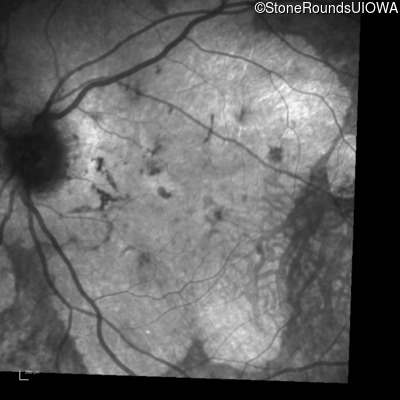

Highlighted Images

Age at visit: 55 years

OD OS